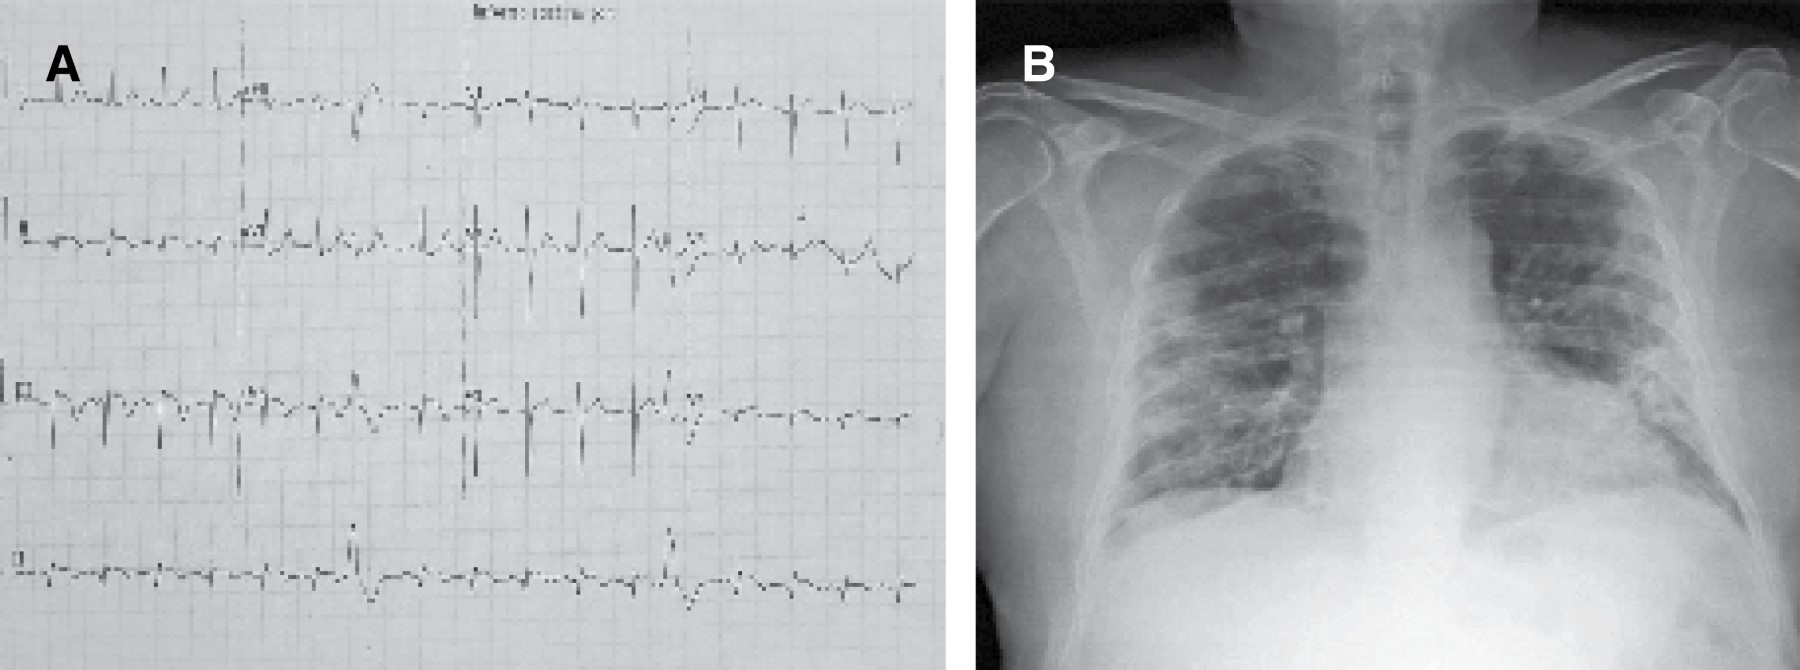

Los análisis de sangre revelaron: leucocitos 6.61 × 103, neutrófilos 5.05 × 103 (76.30%), linfocitos 0.92 × 103 (13.90%), hemoglobina 13.70 g/dL, hematocrito 39%, plaquetas 521 × 103, glucosa 105 mg/dL, BUN 43.6 mg/dL, urea 93.3 mg/dL, creatinina 4.74 mg/dL, TGP 52 UI/L, TGO 89 UI/L, DHL 784 UI/L, CK-MB ≥ 80.00 ng/mL, MYO ≥ 500 ng/mL, TNI 20.8 ng/mL, dímero D 4.09 μg/mL, ferretina 1,817.10 ng/mL, procalcitonina 0.48 (Tabla 1). Un electrocardiograma de 12 derivaciones mostró elevación del segmento ST en DII, DIII, aVF de 1.5 mm (Figura 1A). Los hallazgos en la radiografía de tórax se encontraron con múltiples infiltrados bilaterales diseminados (Figura 1B). Tomografía simple de tórax mostró parénquima pulmonar con patrón dominante en vidrio despulido de distribución periférica bilateral con predominio en hemitórax izquierdo, asociado a engrosamiento septal inter e intralobulillar conformando un "patrón en empedrado", dilatación vascular y bronquiectasias por tracción (Figura 2). Se realizó PCR para SARS-CoV-2 por los hallazgos radiológicos y tomográficos.

Figura 2